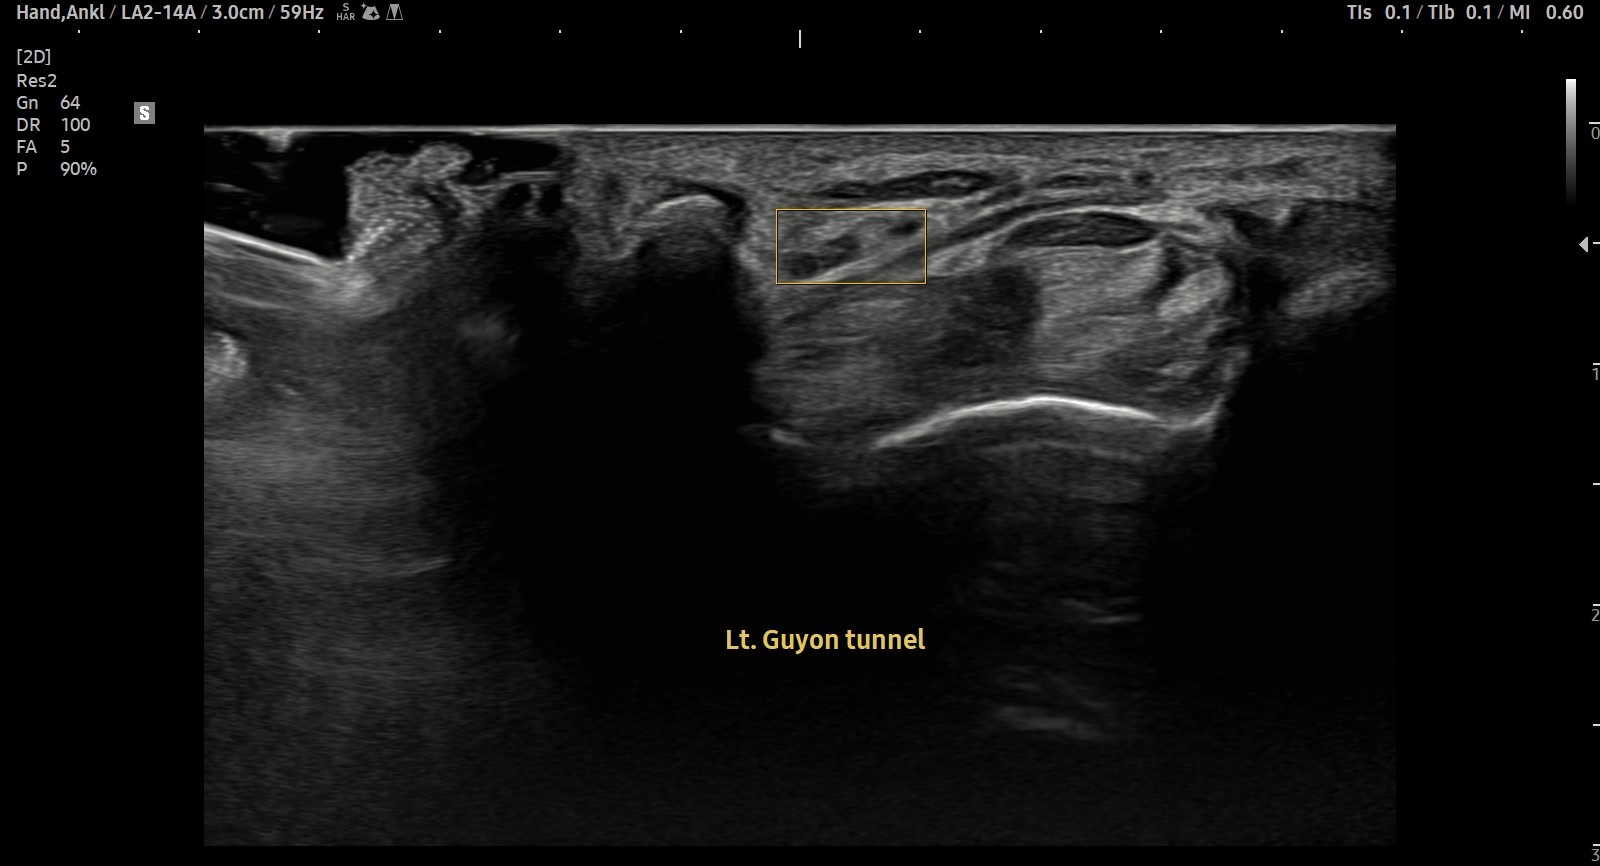

- 치료기간 : 25. 7 . 15 ~ 25. 11 . 18

- 치료횟수 : 25(5cycle) 회

[후기]

치료 전

치료 후